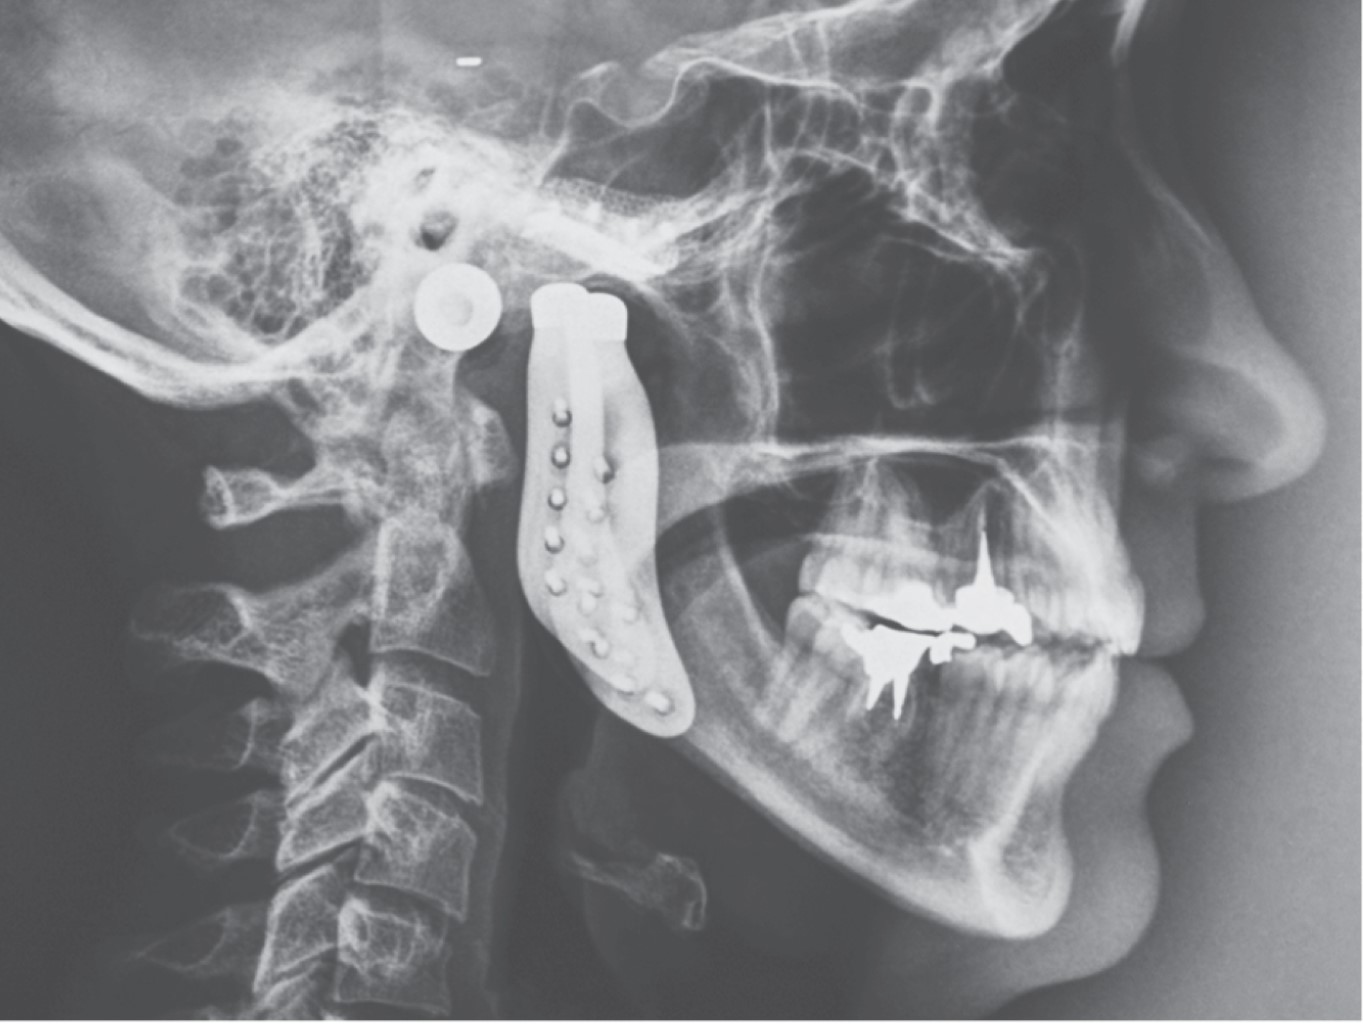

Introduction: the objective is to present a case of total alloplastic replacement of the temporomandibular joint with personalized prostheses (TMJ Concepts®) in rheumatoid arthritis and injection of botulinum toxin type A for protection of prostheses against bruxism. Clinical case: we present the case of a 44-year-old female patient with severe bilateral temporomandibular joint (TMJ) resorption due to advanced stages of rheumatoid arthritis, which was managed by total replacement with a personalized alloplastic prosthesis (TMJ Concepts®, Ventura CA) and infiltration of botulinum toxin type A (Botox, Allergan, Ireland). Results: painful symptomatology was eliminated immediately and pre-surgical oral opening changes from 2 to 50 mm were achieved in the first year after botulinum toxin placement; 12 years later, the prosthesis is stable and functional. Conclusions: botulinum toxin can be a simple, safe, and effective adjuvant treatment in patients reconstructed with personalized alloplastic prostheses.

Figure 3

Figure 4